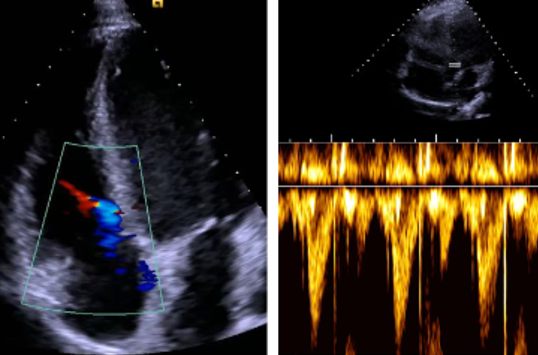

As part of the project, a comprehensive study was conducted with 20 healthy test subjects in which electrocardiogram (ECG) data inside the MRI scanner as well as impedance cardiogram (ICG) data and echocardiogram data outside the MRI scanner were recorded simultaneously. The resulting signal database is unique and includes data at rest and under mild stress. The analysis of this data showed that characteristic cardiac time points such as the pre-ejection time (PEP) and the left ventricular ejection time (LVET) can be reliably derived from the magnetohydrodynamic (MHD) effect of the ECG signal.

Figures: (1) ECG and ECG hardware, (2) specially developed ECG electrode, (3) echocardiogram of a test subject as a Doppler sonogram and (4) as a 3D data set.